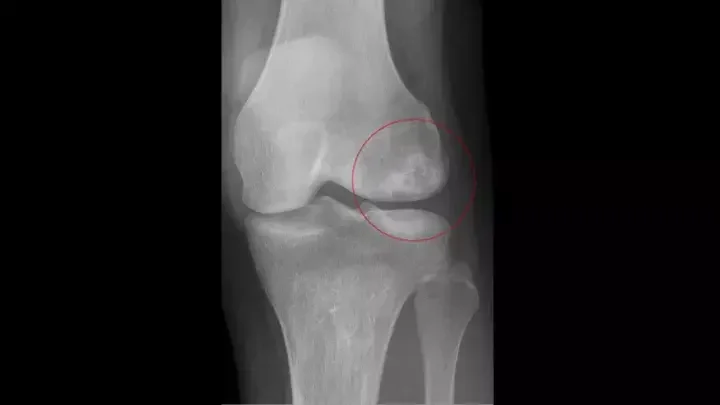

Avascular Necrosis of the Knee